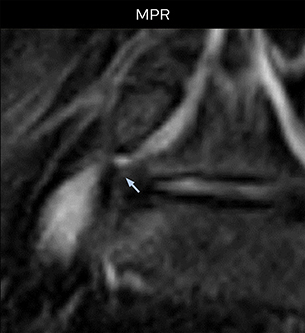

“For example, in sagittal images, when the presence of fat is observed in the intervertebral foramen, it suggests that there is a margin around the nerve. Similarly, the absence of fat indicates that the nerve is being compressed. So, we used to deduce nerve compression indirectly. With NerveVIEW, however, we can observe the condition of the nerves directly, regardless of the presence or absence of fat. We always prefer such direct observation of anatomy over having to make an inference about it.”

“Although symptoms of typical disc herniation and atypical hernia are very similar, the actual site of herniation is different. It is therefore important to characterize the nerve’s condition both inside and outside of the intervertebral foramina. “Conversely, if we see no abnormality in NerveVIEW, we can assume at least that there is no severe condition that requires surgery. Like this, it can help us avoid unnecessary surgery. NerveVIEW can have a tremendous impact in this way.”

“Recently, the two surgical methods extreme and oblique lateral interbody fusion (XLIF and OLIF) have become mainstream for minimally invasive treatment of lumbar spinal canal stenosis and intervertebral foramen stenosis. With these surgical techniques, the spine is approached from the flank, and prior knowledge of the exact anatomy of the lumbosacral plexus would be extremely helpful. To that end, high slice resolution (less than 1 mm acquisition) that enables sharper sagittal MPR images will be needed.”

“For both brachial and lumbar plexus, we are currently using a 230 mm FOV and voxels of about 1 x 1 x 2 mm acquired (1 x 1 x 1 mm reconstructed). This provides us a good representation of the nerves, even though this FOV is relatively small. Regarding the inplane resolution, we hope to be able to bring that down to 0.7 mm, similar to our typical 2D multislice T2W images,” says Tanji.